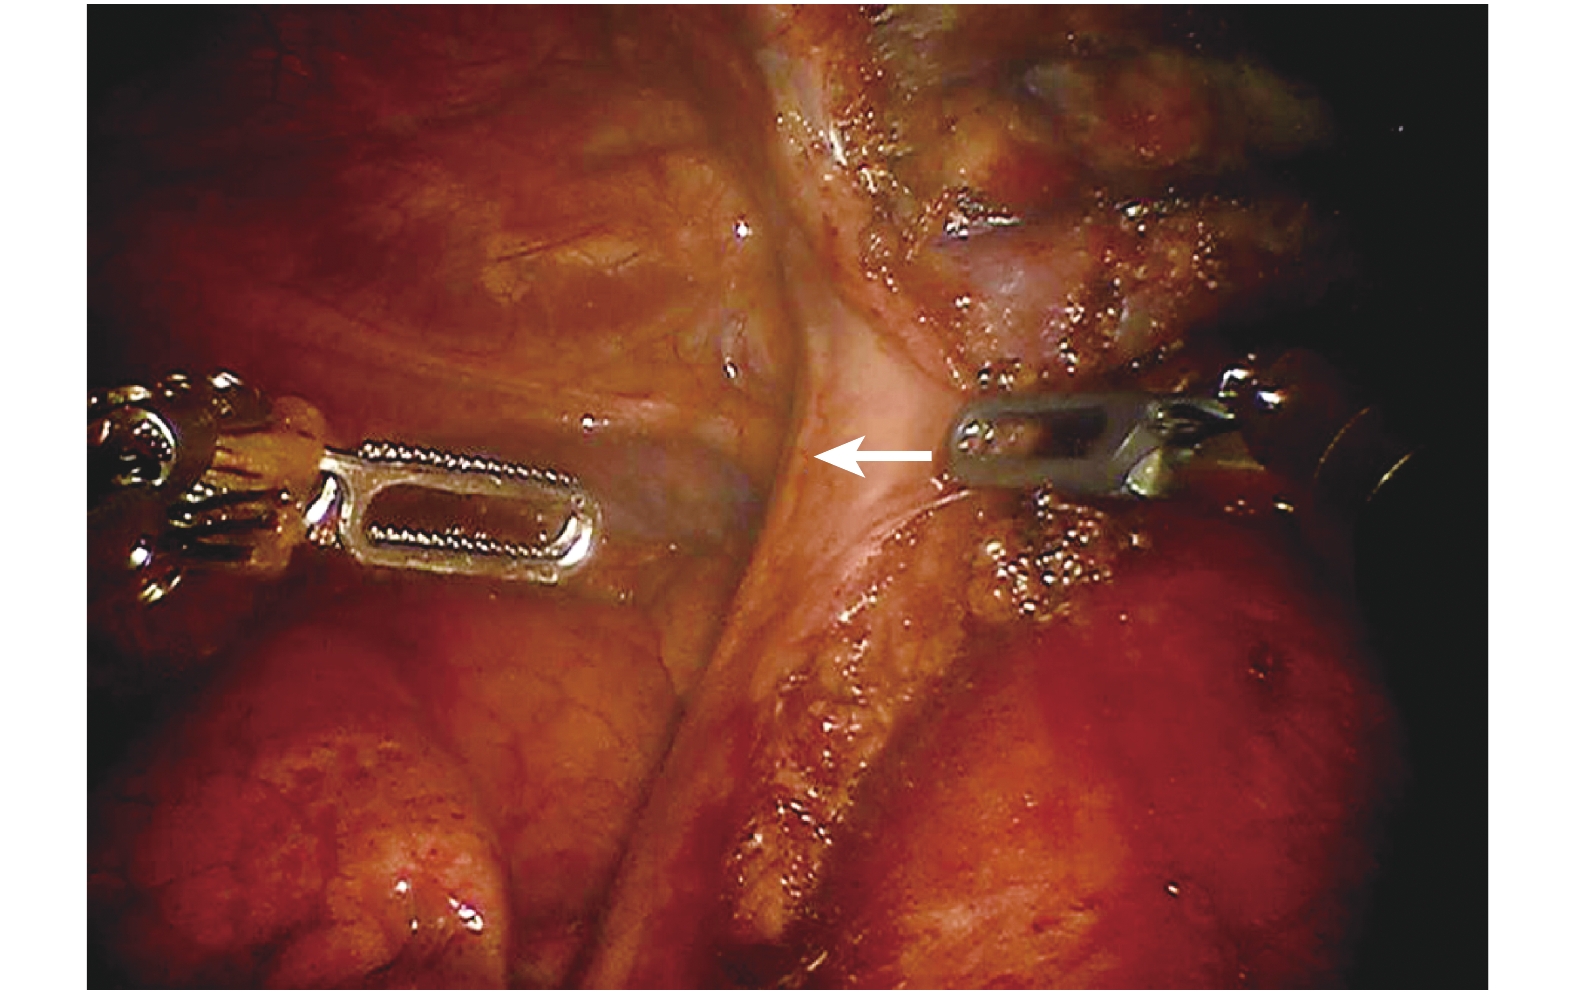

患者取仰臥伴頭高腳低位,單腔氣管插管,靜脈吸入復合全身麻醉。患者體位及切口見圖 1,劍突下做一 2 cm 左右的縱行切口為腔鏡孔,逐層切開皮膚、淺筋膜、腹直肌鞘前層,暴露并保留劍突。手指沿劍突及胸骨后方鈍性分離,使兩側縱隔胸膜之間、膈肌上方及胸骨后方的胸膜外間隙充分擴展,然后在左右兩側鎖骨中線肋緣下置入直徑 0.8 cm 操作孔穿刺鞘至胸膜外間隙,機器人位于患者頭側,其中心柱與患者身體長軸平行(圖 2),分別對接機器人鏡頭臂、1 號和 2 號臂。術中使用 CO 2 人工氣胸,壓力設置為 8 mm Hg。首先,沿胸骨后打開雙側縱隔胸膜,當雙側胸膜腔與前縱隔相互貫通后,于腋前線第 5 或第 6 肋間隙置入直徑 0.8 cm 操作孔穿刺鞘,對接 3 號機械臂。其中從兩操作孔分別置入無創抓鉗進行牽拉暴露,另一操作孔置入超聲刀或電凝鉤等能量器械進行游離或切割,切開雙側縱隔胸膜至左右乳內靜脈匯入無名靜脈處。然后從雙側心膈腳開始,暴露雙側膈神經,沿左右側膈神經(圖 3、4)內側緣向頭側方向,切除心包前方的胸腺及周圍脂肪組織,暴露左無名靜脈匯入上腔靜脈處及左乳內靜脈匯入左無名靜脈處,然后沿左無名靜脈表面從左向右游離胸腺,仔細游離胸腺靜脈,胸腺靜脈大多可以用超聲刀直接切斷,必要時可以用 Hem-o-lok 夾閉。在頸部區域切除左右胸腺上極時,應用有手腕的電凝鉤更為方便(圖 5)。首先顯露出頸根部的甲狀腺下極和胸腺上極,然后向肛側牽拉胸腺上極,從胸腺上極的近端開始向遠端切除頸部胸腺上極及周圍脂肪組織,最后完整切除頸部胸腺的左右上極。此時在左無名靜脈上方,頭臂干、右頸總動脈和氣管均已暴露(圖 6)。若腫瘤同時侵犯心包、肺、左無名靜脈、膈神經等組織或器官時,可同期行心包部分切除、肺楔形切除、左無名靜脈成形或離斷及膈神經切除。若為重癥肌無力患者,同時行胸腺周圍前縱隔脂肪組織切除,切除胸腺周圍的異位胸腺組織。最后,從劍突下切口取出手術標本,檢查無出血后,從一側肋弓下切口安置胸腔閉式引流管,逐層關閉手術切口。